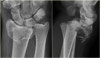

X-ray : 원위 요골 골절(Die-punch fracture)

X-ray : 원위 요골 골절(Chauffeur's fracture)

5. Diepunch 골절 : 월상골 또는 주상골 반대쪽으로 관절면이 함몰되는 골절입니다.

4. Chauffeur's 골절 : 요골 경상돌기 바닥을 사선으로 통과하는 골절입니다.